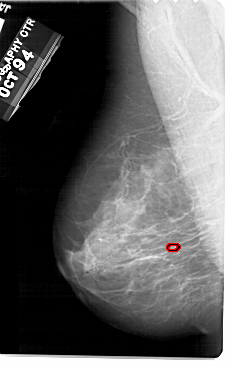

A_1945_1.LEFT_MLO

LEFT_MLO LINES 5491 PIXELS_PER_LINE 3391 BITS_PER_PIXEL 12 RESOLUTION 43.5 OVERLAY

FILE: A_1945_1.LEFT_MLO.OVERLAY

TOTAL_ABNORMALITIES 1

ABNORMALITY 1

LESION_TYPE CALCIFICATION TYPE PLEOMORPHIC DISTRIBUTION CLUSTERED

ASSESSMENT 4

SUBTLETY 2

PATHOLOGY BENIGN

TOTAL_OUTLINES 1

BOUNDARY